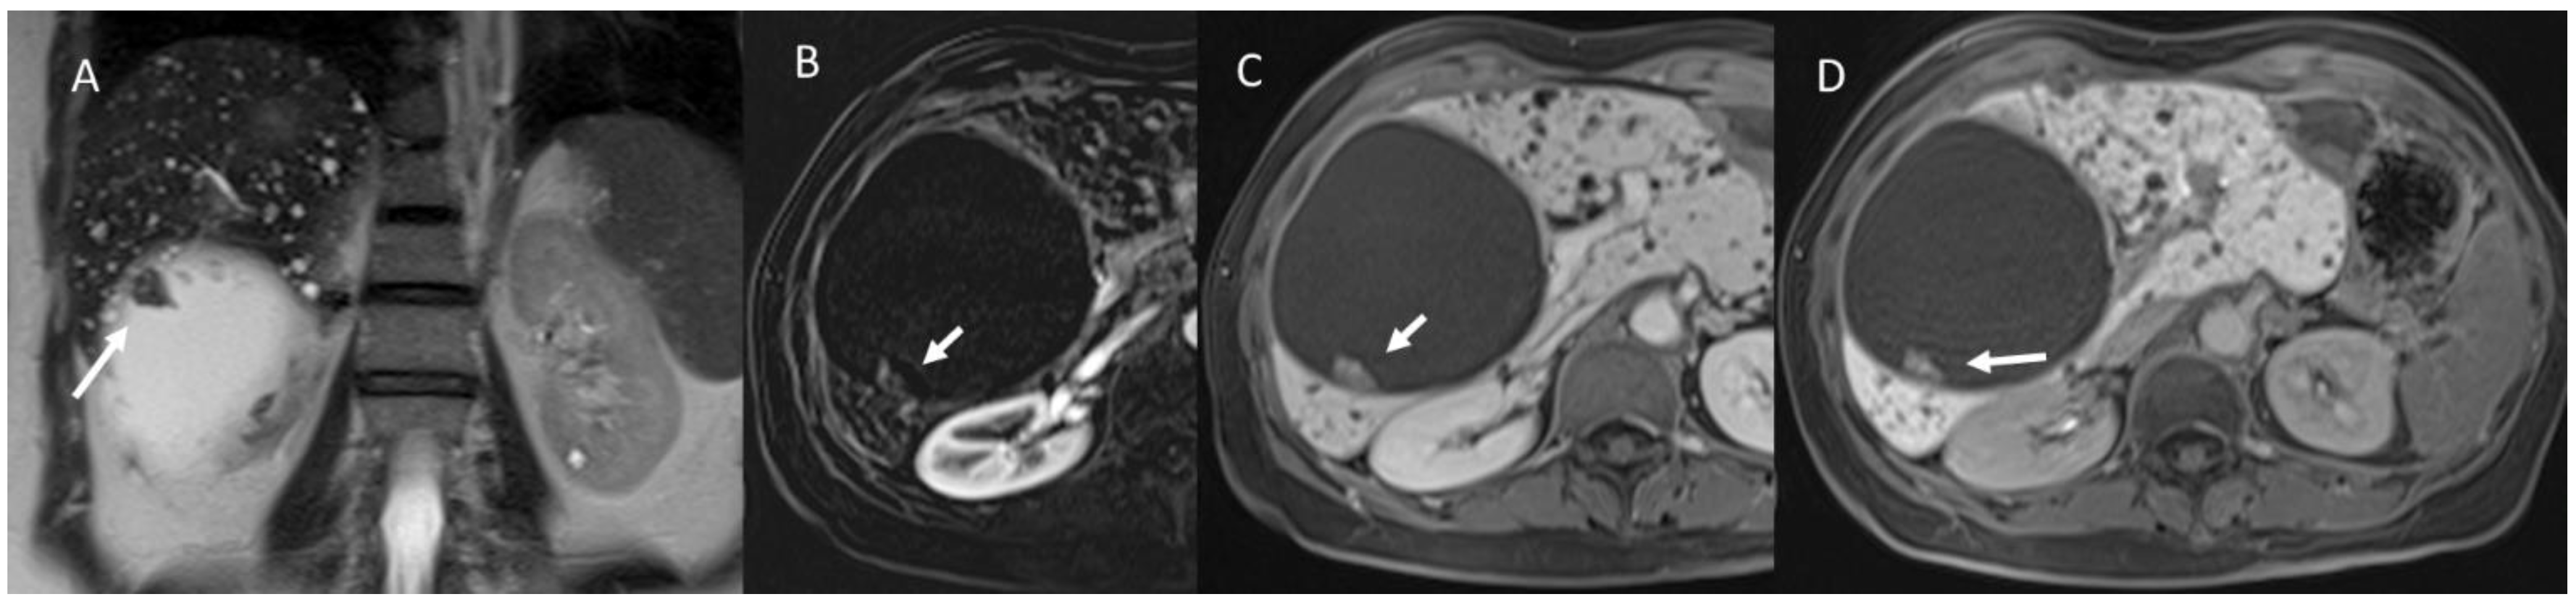

4. Fibropolycystic Liver Disease

6.2. Intraductal Papillary Neoplasia of the Bile Duct

6.3. Intraductal Tubulopapillary Neoplasms of the Bile Duct

6.4. Hepatobiliary Mucinous Cystic Neoplasm

6.5. Diagnostic Management